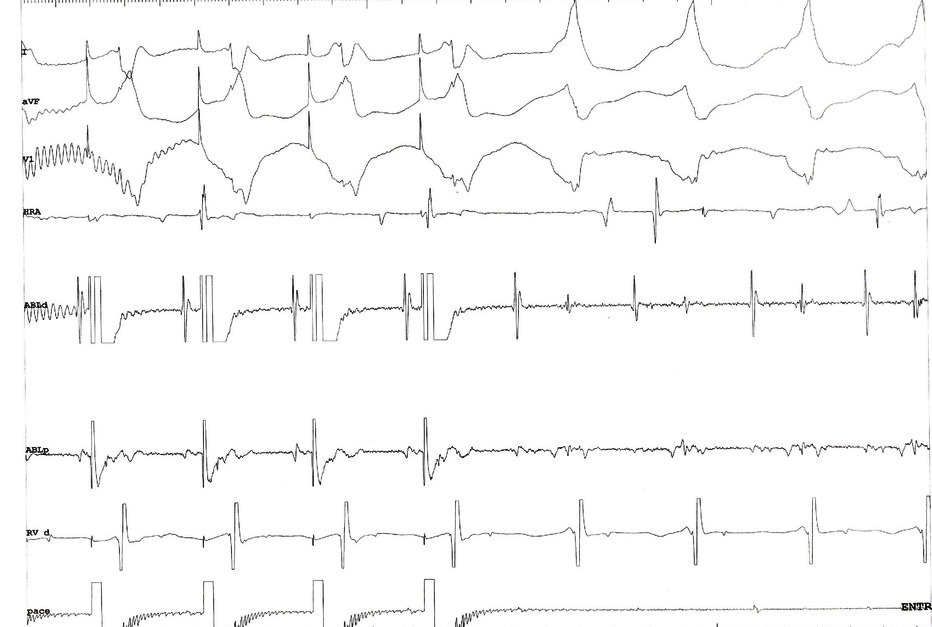

Double potentials = pace to identify

entrain_rv.jpg

• EP maneuvers - analyze tachycardia, ctivation sequence, entrainment

• Choose reference